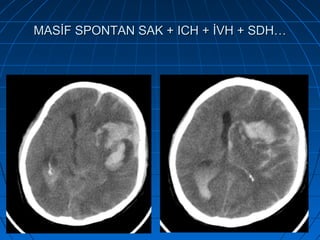

MASİF SPONTAN SAK + ICH + İVH + SDH…MASİF SPONTAN SAK + ICH + İVH + SDH…

MASİF SPONTAN SAK + ICH + İVH +…MASİF SPONTAN SAK + ICH + İVH +…

• 58 yaşında bayan hasta58 yaşında bayan hasta

• Ani bilinç kaybı şikayetiyle acilAni bilinç kaybı şikayetiyle acil

polikliniğe getirildipolikliniğe getirildi

• İlk NM:İlk NM: Bilinç kapalı; GKS: 5Bilinç kapalı; GKS: 5

Pupillalar anizokorikPupillalar anizokorik

YBÜYBÜ

5. günde exitus5. günde exitus